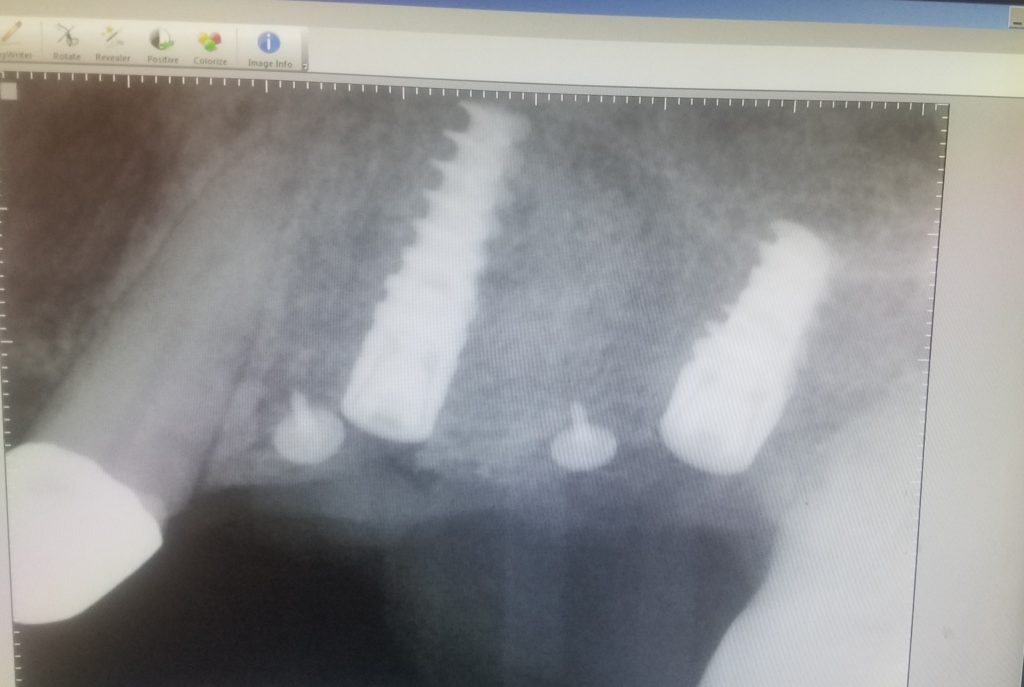

This x-ray is of the two implants I placed for Tina. The two white circular objects are bone tacks securing the bone graft in place.

So, we decided upon a treatment plan that included yesterday’s three and a half-hour appointment during which I surgically placed the implants accompanied by a fairly large bone graft in the adjacent area. Although Tina had sufficient bone to place the implants, I reinforced the existing supporting bone with more volume to ensure long-term success.